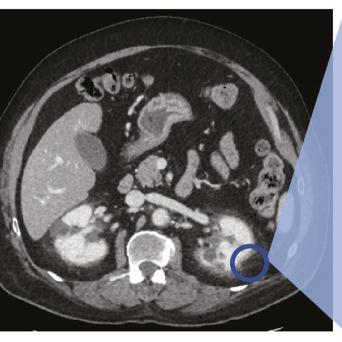

L’image

du jour